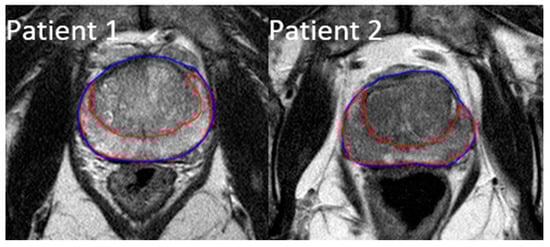

All of the patients received a high-resolution T2-weighted MRI scan in the pelvic region at diagnosis. The images were taken using Philips Medical Systems Achieva 1.5 T MRI scanners with a 2 mm slice thickness. Using Velocity software (Varian Medical Systems, Palo Alto, CA, USA), each MRI scan was manually contoured on two separate ROIs: the prostate gland and the peripheral zone of the prostate. The whole prostate gland is the most common region reviewed by radiologists and also easy to contour for future studies, while the peripheral zone is where over 90% of prostate cancers develop [30]. Figure 1 shows the created contours on two example patients, with the prostate gland outlined in blue and its peripheral region outlined in red.

Figure 1. Example contours of the prostate region of interest (ROI) (blue) and the peripheral zone ROI (red).